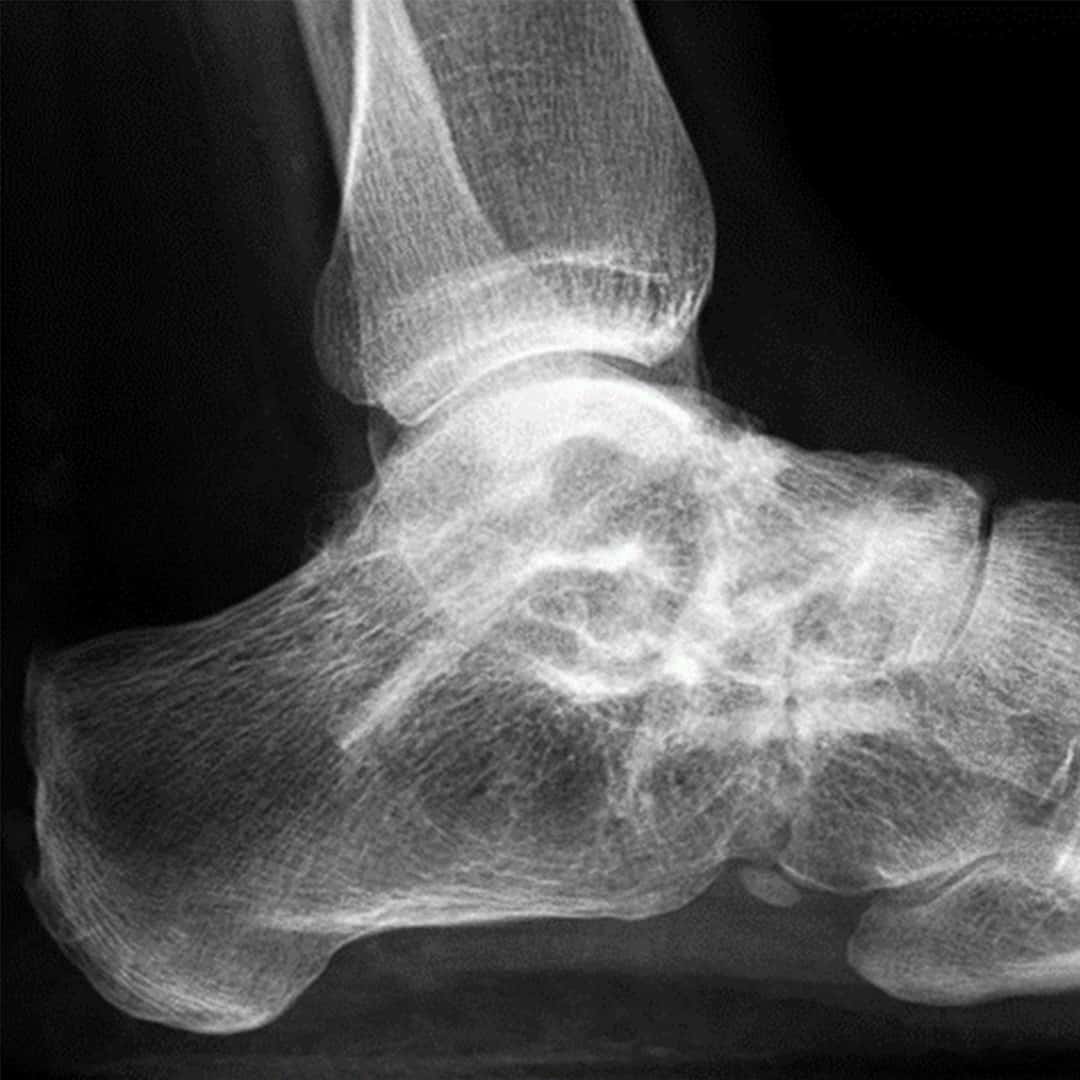

Triple-Arthrodese 12 Monate postoperativ mit Shark Screw®